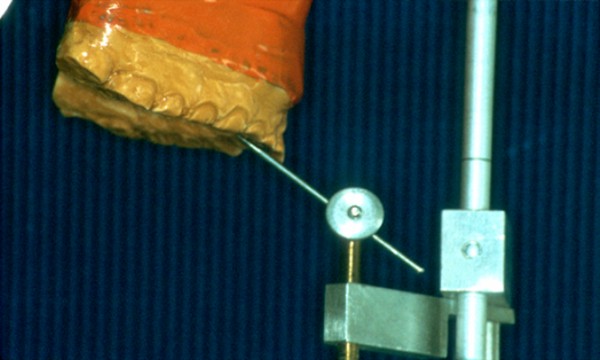

INTRODUCCIÓN El Bruxismo como entidad somática asociada al stress, responde a la mecánica de un Círculo Vicioso Patogénico, que Kawamura describiera hace ya muchos años. FACTOR DESENCADENANTE , que proveen las Interferencias a nivel dentario. En las entregas anteriores se desarrollaron las bases conceptuales de una OCLUSIÓN ORGÁNICA y los efectos de una mayor o menor Desoclusión según la variabilidad de los diferentes Factores Determinantes de la Oclusión. En síntesis; A-La obtención de una Oclusión en Relación Céntrica, nos permite devolver al sistema una elongación muscular fisiológica, sin acortamientos ni estiramientos musculares, sin las consecuentes estimulaciones de los husos neuro musculares, y; una situación estable de la A.T.M. con espacios articulares uniformes. B-El logro de una Guía Anterior que permita desocluir los sectores posteriores durante los movimientos excursivos, nos provée de una segunda y preponderante senda a transitar, que NO estimula por sus contactos excursivos la cincha Pterigo Maseterina, causante de las enormes destrucciones parafuncionales que es frecuente ver en bocas bruxómanas, y la axialización de las fuerzas sobre las piezas posteriores durante el cierre. C-Otorgando como consecuencia, Estabilidad a la tabla premolar-molar, simultaneidad en la recepción de fuerzas durante el cierre(A.T.M. y superficies oclusales). Obtendremos así una Oclusión estable y fisiológica, que no genere el FACTOR DESENCADENANTE del Bruxismo, siempre presente a nivel dentario. INTRODUCTION Bruxism as a somatic entity associated with stress responds to the mechanics of a Pathogenic Vicious Circle, described by Kawamura many years ago. Summarsing: A-Obtaining an oclusion in a Central Relation, allows us to return to the sistem a physiological muscular elongation, without muscular shotthenings or lenghthenings, without the following stimulations of the neuro-muscular huses and a stable situation of the Temporo Mandibular Joint with uniform articular spaces. B-The accomplishment of an Anterior Wide wich may allow disclusive the posterior sectors during the excursives movements, and the axial forces during the mandibular closure. C-Providing as a consecuence, axiality and stability to the posterior sections, responsible of the mandibular closure, through Sttopers, Equalitzers, A, B and C, to obtain a Oclusión Mutuamente Compartida: forces reception during mandibular closure (T.M.J. and Oclusal Surfaces) By this procedure, we should obtain a stable and physiological oclusion, that will not generate the chain link of factors that lead to Bruxism, always present at the dental level. MATERIALES Y MÉTODOS: La funciones articular y muscular, se analizaron mediante Bio Pack, en el pre, en el intra y en el post operatorio. Durante el diagnóstico, tratamiento y remontas, se utilizaron articuladores semi ajustables Wip Mix, totalmente ajustables Artex y arcos faciales correspondientes. El encerado de dianóstico se realizó, mediante la técnica de encerado progresivo de Peter K. Thomas. Los refuerzos a Perno Colado se llevaron a cabo con oro BIODENT YELLOW de ARGEDEN. Los tres juegos de provisionales utilizados, se hicieron con metacrilato termo curado. Las Restauraciones Periféricas Totales, fueron realizadas mediante porcelana CREATION de WILLY GUÉLLER, sobre oro BIODEN YELLOW de ARGEDEN. Los chequeos de los Contactos Interoclusales, se midieron con papeles de articular de 40 y 12 micrones, y mediante el analizador computarizado T-Scan. DESARROLLO Paciente varón de raza blanca, 42 años, complexión robusta y marcada hipertrofia maseterina. Fig.1 Fig.2 Fig.5 Se realiza un análisis pre-operatorio articular y muscular mediante Bio Pack, y oclusal mediante T-Scan, cuyos resultados muestran una evidente hiperactividad muscular en Temporal Anterior y Masetero Derechos, y contactos totalmente anómalos tanto en Oclusión Habitual como en Excéntricas. Fig. 6-7-8-9-10-11 Sensor de ruidos articulares Luego del primer intento de relajación mediante Laminillas de Long (Ref.6),Fig.12, registros y montaje, se observa la aparente presencia de una relación Borde a Borde, que luego se comprobaría que se trataba de una propulsión exagerada de su mandíbula en la búsqueda de contactos efectivos. Fig. 13-14 (Obsérvese el fenómeno de Patterson dado por la exclusiva guía de movimiento de la A.T.M. y la carencia de la Guía Anterior) Se procede a construir un JIG de LUCIA para lograr una desprogramación muscular adecuada, y se le indica permanecer con el colocado durante toda la noche anterior a la consulta, sin contactos dentarios posteriores. Aún en la duda, de que la obtenida sea una posición articular fisiológica, se procede a construir una Placa de Relajación sobre el último montaje obtenido, la que se ajusta cada dos días, y al cabo de tres semanas se procede a un tercer montaje obtenido de la nueva situación posicional. Fig.17-18 Se verifica entonces que estamos en realidad, ante una presunta CLASE II, después de tres métodos diferentes de relajación y transcurridos más de un més de múltiples sesiones para lograr una posición diagnóstica confiable a partir de donde comenzar a trabajar.(O.R.C.) Se adicionan entonces topes (montículos) en las caras oclusales de los primeros molares de la Placa de relajación, transformándola en una Férula Pivotante, de levísima altura, impidiendo el contacto de las demás piezas dentarias a fin de convertir la palanca en una de clase II (fisiológicamente el sistema se mueve según una palanca de clase III), y obtener de esa forma una descompresión de los espacios articulares, ya que si bien la A.T.M. era asintomática, estaba muy claro que la Dimensión Vertical Posterior se presentaba disminuida debido al exagerado desgaste de todos los sectores posteriores, cuya típica forma de «desgaste en olla», se verificaba en el análisis estático de los modelos.( Ref.7) En esa situación se remonta el modelo inferior puesto que el superior no modifica su posición espacial, y se realiza un Encerado de Progresivo Diagnóstico según PKT, previo análisis de los modelos mediante los analizadores de W.McHorris (Ref.8) Fig.18-19-20-21-22-23-24-25-26-27-28-29-30 Fig.18 Fig.22 Fig.23 (Obsérvese, que la Disclusión Propulsiva comienza en los rebordes mesiales del canino, sigue en los rebordes distales del lateral, y finaliza con los rebordes mesiales de los centrales.) Se realizan las endodoncias de toda la boca y se tallan los endodontos para la construcción de Pernos Muñones Colados de oro, los que se realizarán mediante técnica indirecta sobre los modelos :montados según los logros de todos los procedimientos de relajación. Se torna imprescindible la extracción de tres piezas dentarias, para la confección de la Guía Anterior, cuyo alineamiento hubiera sido imposible mediante técnicas reconstructivas ya que la posibilidad ortodóntica no era viable dadas las condiciones de desgaste. Fig.31-32-33-34-35-36-37 (Obsérvese, que desde la configuración de los Pernos Muñones Colados, se determina ya la Alineación Tridimensional que otorgaremos a la Rehabilitación Oral Integral del caso. Se monta entonces el primer juego de Provisionales de acrílico de termo curado, obtenido de la réplica del Encerado de Diagnóstico. Fig.38-39-40-41 (Obsérvese la presencia del ajuste periférico y las disclusiones, tan importantes en las provisorias como en las definitivas ya que del resultado de la etapa de provisionales, dependerá el éxito final.) Se ajustan las Unidades de Oclusión mediante Ajuste Oclusal (según técnica propuesta por la Cátedra de Operatoria Dental II y Prótesis de la Fac. de Odontología, Univ. Bs. As., Prof.Anibal Alonso.) Se deja actuando la nueva situación durante seis meses. Han transcurrido seis meses durante los cuales se instaló un nuevo juego de provisorios con las mismas características del anterior, y clinicamente no se observa hiperactividad muscular, perforaciones de los provisorios, molestias para desmenuzar los alimentos ni síntomas alguno en la A.T.M. NOS ENCONTRAMOS, CON UN SISTEMA EN PAZ A TODOS SUS NIVELES. Se procede entonces a la toma de impresiones definitivas, mediante la técnica de Impresión a Presión Masticatoria, para la confección de las restauraciones permanentes, y los metales se chequean mediante llaves de Duralay, para observar la situación análoga entre laboratorio y clínica.(Corroboración de la Oclusión en Relación Céntrica)Fig.42-43-44 Se prueban los metales y verifica su ajuste periférico. (Obsérvese que también en los metales sub porcelana se siguen las formas de las Preparaciones Funcionales, permitiendo de esta manera un perfecto bizcochado de la porcelana supra metal.) Realizada la Guía Anterior, Determinante Oclusal Primario y Anterior en el laboratorio, se prueban en boca sus características estáticas: Altura Funcional, Ángulo de la Disclusión y Punto de Acoplamiento, como así las dinámicas: Laterotrusión Derecha e Izquierda y Propulsión. En este estado las cosas, tenemos al sistema circunscripto tanto estática, como dinámicamente, por el gobierno de dos comandos, ya en Oclusión en Relación Céntrica, como en las Transtrusiones: Sabemos que todo lo que construyamos (tabla premolar-molar), entre estos dos comandos rectores del movimiento, partirán del mismo punto y volverán a el, transitando el recorrido impuesto por los mismos. Se construyen entonces en el laboratorio, las unidades de oclusión de premolares y molares, siendo las correspondientes a los cuatro últimos molares, con oclusal en oro, como un elemento de detención del cierre más poderoso que la porcelana.47-48-49-50-51 Se prueban en boca la Curva de Wilson, la Curva de Spee, la Alineación Tridimensional, los Espacios Uniformes Disclusivos, la Dirección de los Surcos de T, nT, y P, y los Puntos Interoclusales de Contacto. En laboratorio se retocan entonces los Puntos Interoclusales de contacto, acercando los mismo a la mejor posición ideal lograble, y luego de una nueva prueba en boca, se glacéan las piezas y se instalan en forma provisional durante 24 hs. Verificada la eficacia de las formas (FORMA=FUNCIÓN), se procede a constatar la eficiencia de la dinámica trayectorial y se cementan con cemento de fosfato mediante la técnica de cementado alterno. Fig.54-55-56-57-58-59-60-61-62-63-64-65-66-67-68-69. Fig.54 Fig.55 Curva de Wilson y Alineación Tridimensional en molares y premolares sup. Der. Fig.56 Fig.57 idem inferiores derechos Fig.58 Fig.59 Idem superiores izquierdos CONTACTOS INTEROCLUSALES SUPERIORES CONTACTOS INTEROCLUSALES INFERIORES Transcurrido un mes de instalada la Rehabilitación, se lleva a cabo un nuevo estudio, post operatorio con Bio Pack y Tscan. CONCLUSIONES : I-El paciente realiza una apertura bucal de 45mm sin forzamientos siguiendo una misma línea de apertura sin desvíos. II-Las disclusiones en laterotrusión se llevan a cabo mediante un recorrido lineal sobre los rebordes medios de ambos caninos superiores, creando un fenómeno de Luce con espacios uniformes en ambos lados. III-La disclusión en propulsión se manifiesta comenzando en los rebordes mesiales de ambos caninos, siguiendo por los rebordes distales de laterales y terminando en los rebordes mesiales de ambos centrales, dando lugar a un fenómeno de Christensen con espacios uniformes de ambos lados. IV-Los contactos interoclusales son suficientes, simultáneos y tripódicos logrando la estabilidad en ambos planos del espacio tanto de las piezas individuales como en conjunto, sin contactos deflectivos. V-Realizado un nuevo montaje de la boca terminada, corroboramos como estable la Oclusión en Relación Céntrica. VI-No existen movilidades dentarias y los tejidos periodontales y gingivales se encuentran estabilizados. VII-No existen ruidos articulares. VIII-El resultado post operatorio Bio Pack de la dinámica mandibular, muestra una sustancial mejora de los movimientos en los tres planos del espacio. IX-Electromiográficamente, se observan contracciones musculares dentro de los rangos de normalidad, persistiendo un rango ligeramente elevado en temporal anterior y masetero del lado derecho, presumiblemente debido a la hipertrofia que dicho paciente traía, y mostraba en el estudio pre-operatorio. COMPARACIONES PRE, INTRA Y POST OPERATORIAS Sonografía de la ATM: Tanto en el examen pre como post operatorio no se observaron ruidos de ningún tipo, coincidiendo con la exploración clínica pre auricular e intra auricular. Electromiografía: La electromiografía en reposo, muestra bien a las claras la presencia de músculos hipertónicos durante el estudio pre operatorio, fundamentalmente del grupo Temporal Anterior y Digástricos, estando el Masetero izquierdo ligeramente por encima de su rango normal como así también ambos Esternocleidomastoideos. Durante el estudio post operatorio, se verifica el estado tónico de todos los grupos musculares, persistiendo una ligera hipertonicidad de rango levemente por encima de lo fisiológico, en el Temporal Anterior Derecho y Digástrico Derecho. PRE OPERATORIO POST OPERATORIO Temporal Ant. Der. 4.4 2.8 Temporal Ant. Izq. 6.2 1.1 Masetero Der. 1.2 0.5 Masetero Izq. 1.5 0.8 Est.Cleid.Mast. Der. 1.6 0.3 Est.Cleid.Mast. Izq. 2.1 0.2 Digástrico Der. 1.7 2.9 Digástrico Izq. 1.6 0.7 (La unidad de medida utilizada es el microvoltio ) Dinámica mandibular: Durante el Pre Operatorio, en el Plano Sagital, tanto la Apertura como el Cierre lento, se manifiesta mediante una acentuada tendencia a propulsar la mandibula. Durante el Post Operatorio, la tendencia hacia la derecha de estos dos últimos planos se mantiene, mientras que en Plano Sagital, la propulsión inicial no se produce, asemejándose el movimiento a la primera fase del Bicuspóide de Posselt. El Análisis de la Dinámica realizado durante la Masticación (chicle), nos muestra en el Plano Sagital, la propulsión mencionada durante la apertura y cierre lentos durante el estudio Pre Operatorio, se aproxima a la normalidad durante el Intra Operatorio (2º juego de provisionales), y se vuelve a manifestar propulsivo, en el Post Operatorio. En cuanto al Plano Frontal, durante el Pre Op. , ofrece un Ciclo Masticatorio(recordar la forma de «gota de agua») para el lado izq., con componentes derechos e izquierdos alternos, que se aproximan paulatinamente al Ciclo Masticatorio Normal, durante el Intra y Post Operatorio. El Plano horizontal, confirma las afirmaciones anteriores durante los tres períodos de estudio. ANÁLISIS MEDIANTE TSCAN 1-Bio Pack Bio Research Associates,Inc Distrib.UEDA S.A. 2-Wip Mix-Artex 3-Au:89% / Pt:6% /Elementos complementarios:5% 4-Idem ref.3 5-Tscan TekSkan,Inc Distrib.UEDA S.A. 6-Mc Horris.Cátedra de Operatoria Dental II y Prótesis. 7-Alonso.Cátedra de Operatoria Dental II y prótesis. 8-Mc.Horris. Analizadores de Guía Anterior. BIBLIOGRAFÍA: 1-Esquemas de las dos primeras entregas, tomadas del libro:»Oclusión Orgánica…un camino hacia la Rehabilitación Oral» 2-Oclusión y Diagnóstico en Rehabilitación Oral. 3-Anatomia Odontológica. 4-A contribution to the study of the movementes of the mandible. 5-Celenza F.W, Nadeskin J.F.,Oclusión.Situación actual. 6-D´Amico 7-Dawson P.E. 8-Huffman -Regenos. 9-Hobo S.-Takayama H.A. 10-Lucia V.O 11-Mc Horris. 12-Mc Horris. 13-Posselt U. 14-Stuart C. 15-Vartan Veshnilian AGRADECIMIENTOS: La Rehabilitación Oral, especialidad donde se hace imprescindible el manejo y concurrencia de todas las especialidades dentales en su desarrollo más depurado, no tendría razón de ser, sin la más estrecha colaboración de una técnica para- médica con detalles de excelencia. Sr. Pedro Colomina: muchas gracias. Pedro Colomina. – Titulado especialista en prótesis dental en la escuela Ramon y Cajal de Barcelona 1988

La Guía Anterior es inexistente y el desgaste premolar-molar nos habla de una pérdida de Dimensión Vertical , tanto anterior como posterior.Fig.1-2-3-4-5

Analizador de Guía Anterior

Fig.20

Punto de Acoplamiento

Canino

Fig.21

Acción Centralizadora

Canina

Verificación de la acción canina Der. e Izq.

Oclusión en Relación Céntrica

(Derecha)

Fig.24

Disclusión Canina

(Derecha)

Fig.25

Oclusión en Relación Céntrica

(Izquierda)

Fig.26

Disclusión Canina

(Izquierda)

Fig.27

Aprobados dichos chequeos, se procede a realizar una técnica de REMONTA, consistente en fijar a una plancha de metacrilato sin variación dimensional, y rebasado con pasta cinquenólica, a las superficies oclusales colocadas en boca.

Construimos dos nuevos modelos que nos muestran la exacta posición de nuestras restauraciones, y mediante los ya mencionados métodos de relajación (Lam. De Long), procedemos a un nuevo montaje en articulador. Fig.52-53